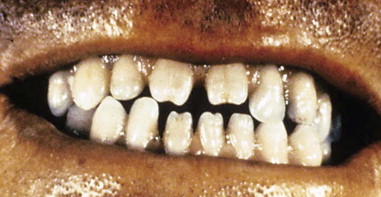

What causes this?

Tetracycline taken by the mother during pregnancy